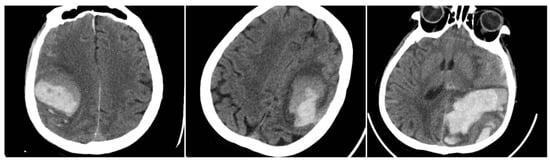

Irregular Shape (IRS) has a clearly lobulated or spiculated hematoma margin, interpreted as multifocal bleeding sources (IRS = 1 if irregular, otherwise 0) (Figure 3) [11].

Figure 3. Irregular Shape sign—three examples from our cohort.